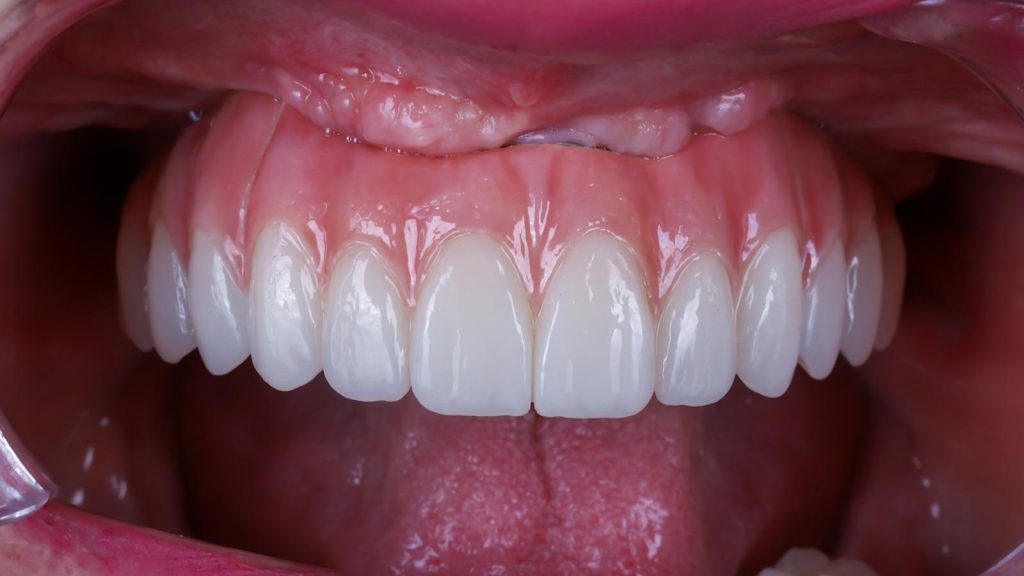

Implantes transnasales fotos y resultados

Te mostramos algunos casos reales tratados en nuestra clínica con implantes transnasales.